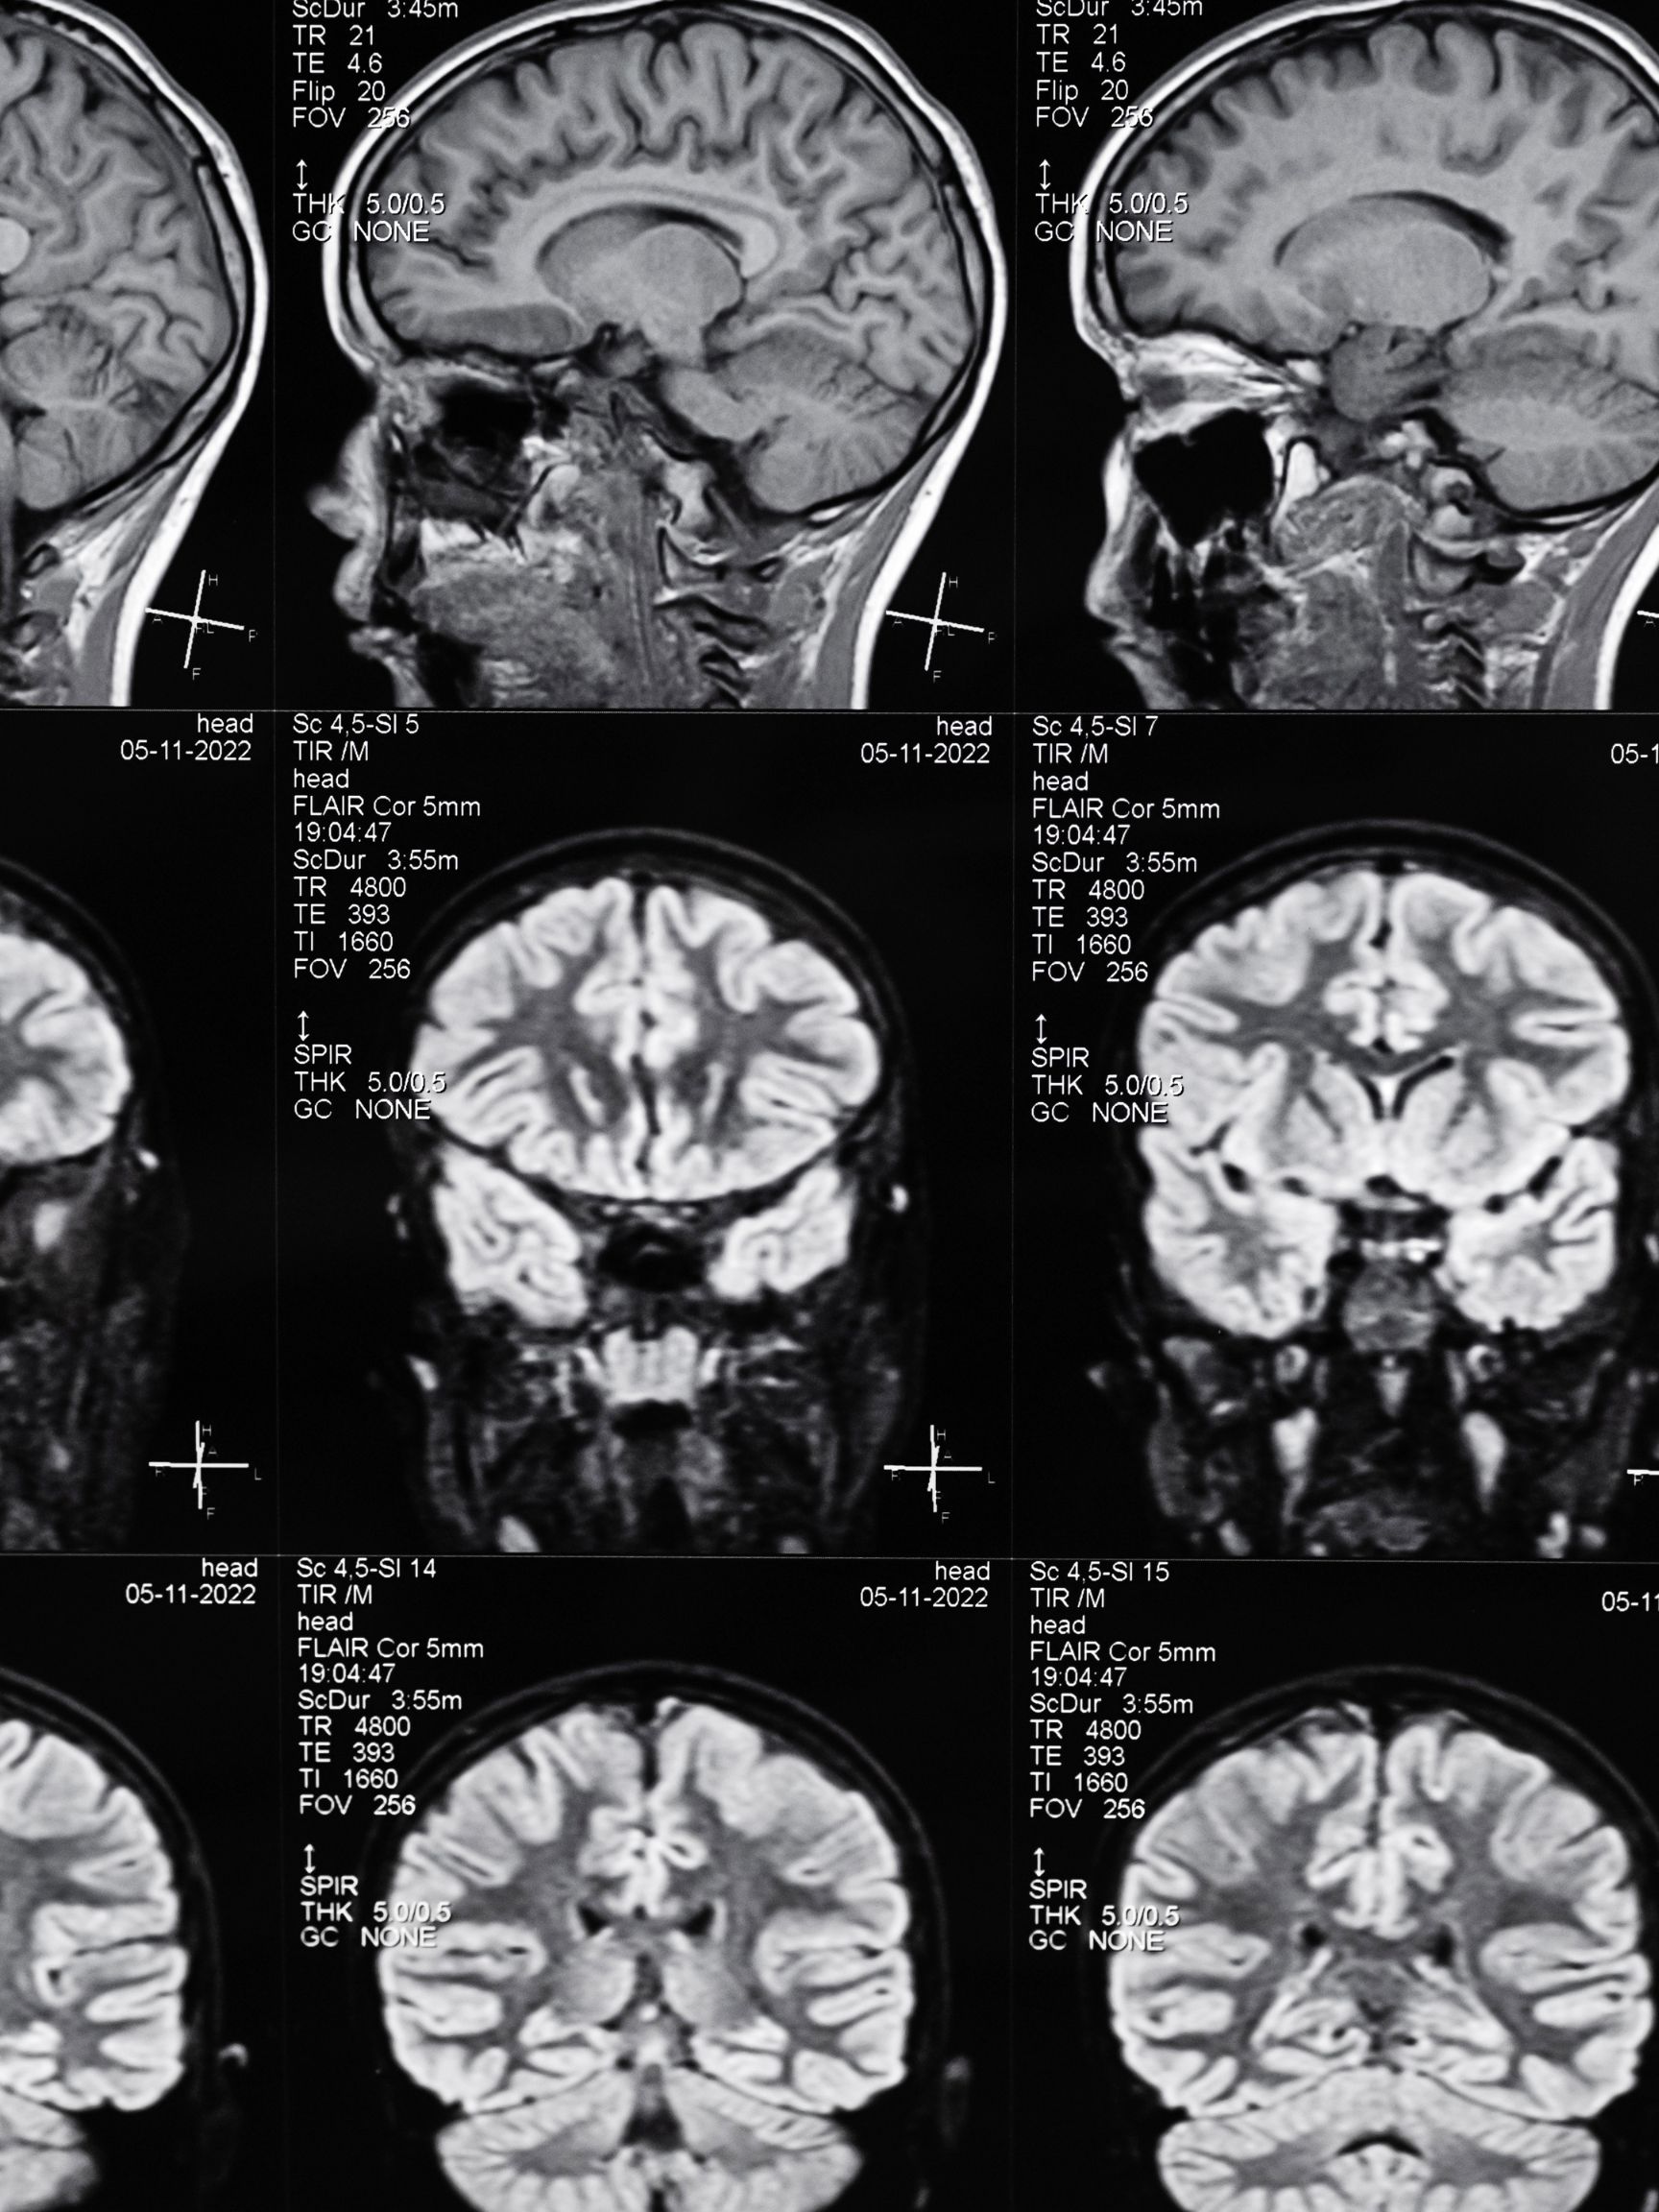

Living with a traumatic brain injury (TBI) can be an overwhelming and life-altering experience. The aftermath of such an injury, often resulting from events like a car accident or medical malpractice, can lead to so many different challenges, both physically and emotionally.

Brain injuries are not to be taken lightly. Some incidents might seem minor at first but can lead to traumatic brain injury. In 2020 alone, there were over 200,000 TBI-related hospitalizations. In 2021, there were almost 70,000 TBI-related deaths.